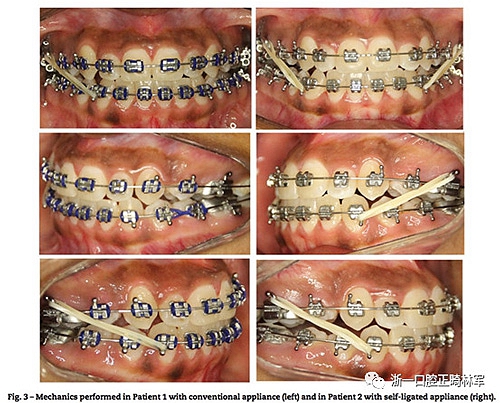

患者1使用0.022的Roth傳統(tǒng)矯治器。弓絲序列為0.014,0.016,0.018NiTi絲;0.018,0.02,及0.018×0.025的不銹鋼絲。治療初期拔除前磨牙,隨后在側切牙和尖牙間使用NiTi開口彈簧,間隙打開后側切牙上粘托槽,使用0.012NiTi,12月后牙排齊,關閉拔牙間隙,未使用支抗釘(圖3)。后12個月使用橡皮筋牽引直至矯治器移除,整個階段維持了24個月,期間每月復診(圖4)。

患者2使用0.022的Roth自鎖托槽,弓絲序列為0.014,0.016,0.018熱激活NiTi絲;0.018,0.02,及0.018×0.025的不銹鋼絲,治療初期拔除前磨牙,隨后在側切牙和尖牙間使用NiTi開口彈簧打開間隙后用NiTi絲排齊,排齊整平時間用了14個月,后期使用橡皮筋牽引微調,整個階段維持24個月(圖3,圖5)。